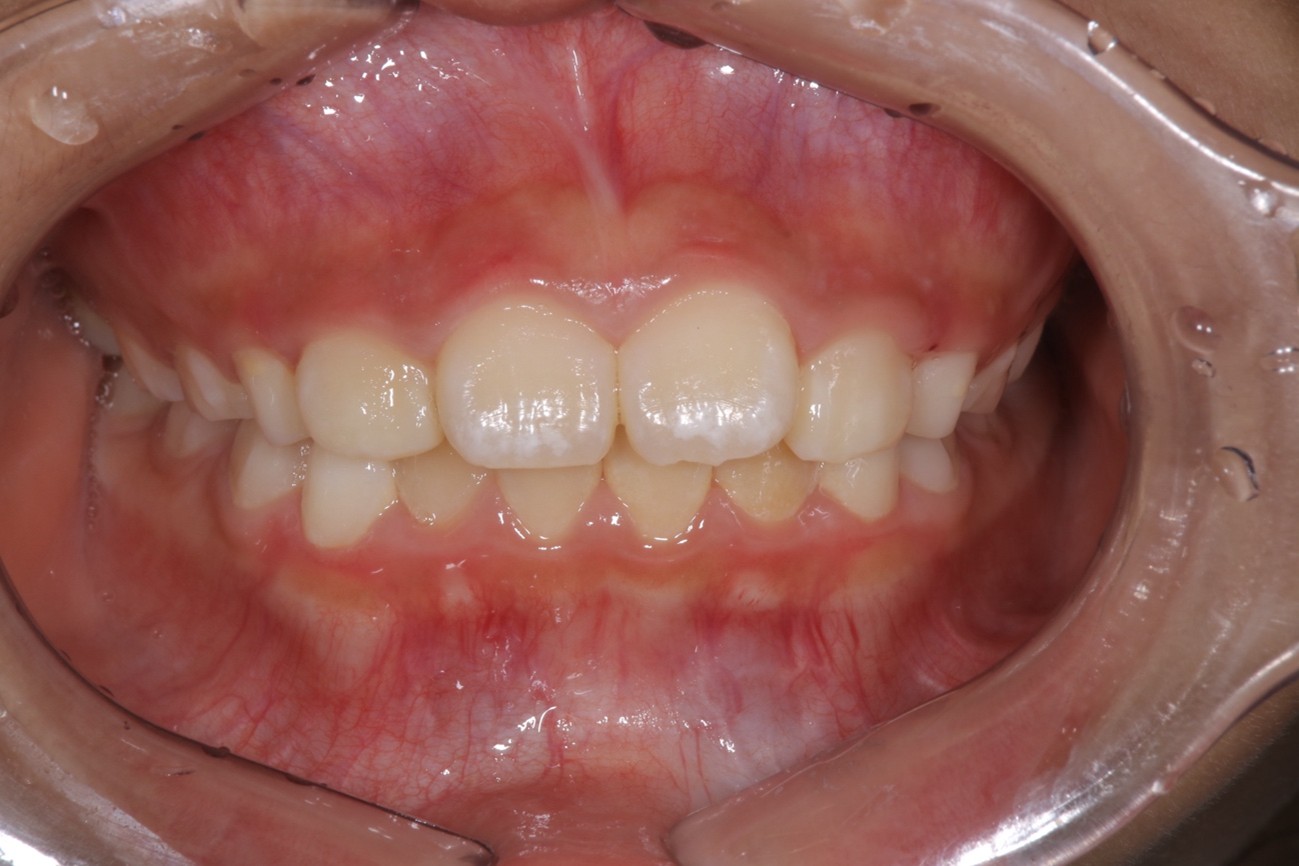

Before